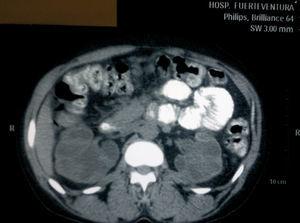

We present the case of a female patient, 41 years of age, with no significant past medical history, who was sent from the emergency department due to deterioration of renal function with serum creatinine (SCr) of 6.5mg/dl, in the setting of vaginal bleeding requiring transfusions. At that time, she was diagnosed with uterine fibroids by the gynaecology service. She was admitted for further work-up and a renal ultrasound was performed, showing grade IV bilateral hydronephrosis, with poor corticomedullary differentiation, but without visible ureters, for which a CT scan was performed. The CT showed grade IV bilateral ureterohydronephrosis secondary to extrinsic compression by the myomatous uterus, which measured 13 x 9cm (Figures 1 and 2). The urology service was notified, which placed a double “J” catheter in the right ureter, but was unable to place one in the left ureter. Evaluation by the gynaecology service was requested, which postponed a simple hysterectomy to the following week.

Figure 1. CT cut where bilateral hydronephrosis can be seen.